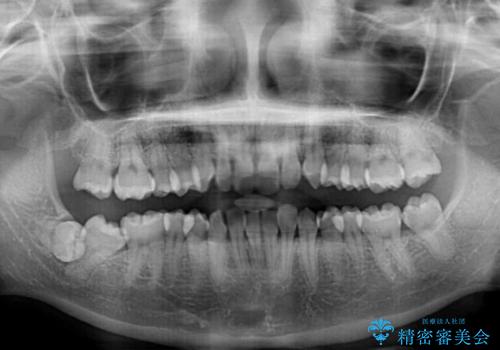

- 前歯のデコボコと歯肉に埋もれている奥歯を気にして来院された患者様です。

インビザラインでの治療を希望されていましたが、左右の下顎大臼歯が歯肉に埋もれており、特に右側は歯軸が顕著に傾斜していたため、インビザライン単独での治療は困難と判断し、ワイヤー装置を併用することとしました。

ワイヤー装置を併用したことで、レントゲン写真からも分かるとおり歯軸をしっかりと改善させることができました。